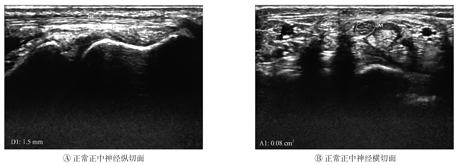

超声检查结果表明,在高频超声下,CTS组与对照组手腕的正中神经均可连续全程探及,并可追踪至肘部(图1A);正中神经在腕管入口、中部及出口处横切面均呈圆形或呈扁椭圆形,内有强回声散点状分布,周围呈高回声包绕(图1B)。CTS组的患腕腕管处正中神经肿胀增粗,内部结构分布不清,高回声减低(图2)。